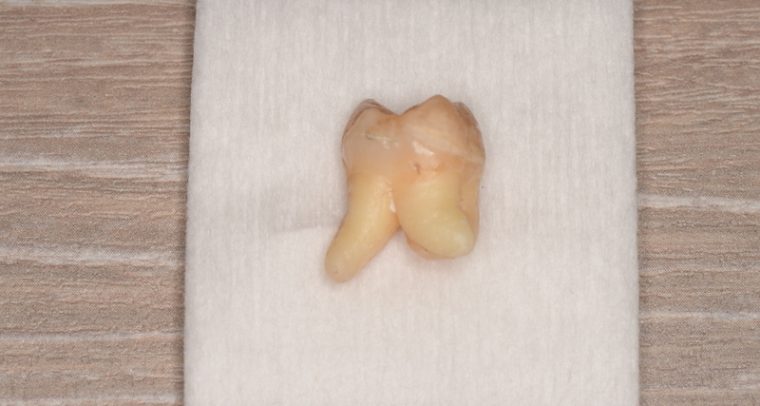

CASE 1

基本情報

| 年齢・性別 | 30代・女性 |

| 主訴 | 左右に分けて親知らずを抜きたい、できれば痛くなく抜きたい |

| 親知らずのはえ方 | 完全に出ていてまっすぐはえている |

| 抜歯期間 | 15分 |

| 抜歯費用 | 約2,000円(保険内) |

| 抜歯内容 |

何度か虫歯になり痛みはないが早めに抜きたい。 完全に頭が出ているため歯ぐきを切ったり骨を削らずに抜歯しました。 根の形も単純なため抜歯自体は5分もかからず上下ともに終わりました。 術後痛みや腫れも出ていません。 抜歯後は感染をしやすいため必ず抗生物質を飲み切ってください。 |